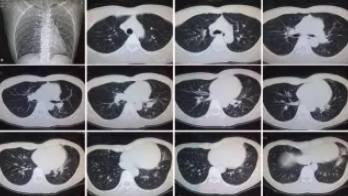

CT檢查原理是X光分層穿過人體,這就像把面包切成薄片,每一片都可以攤開看。當(dāng)遇到外傷懷疑傷到骨頭,可以選擇CT觀察隱匿損傷或軟組織損傷。

CT適用于頭部、胸部、腹部、盆腔、脊柱、四肢、骨骼等處,由于它的特殊診斷價(jià)值,已經(jīng)廣泛應(yīng)用于臨床,特別是在腫瘤的診斷上更是具有很高的應(yīng)用價(jià)值。但由于CT設(shè)備較為昂貴,檢查費(fèi)用也會(huì)偏高,對(duì)于某些部位的檢查和診斷價(jià)值,尤其是定性診斷,還有一定限度,所以在臨床上并沒有將CT檢查視為常規(guī)診斷手段。此外,CT診斷輻射量大于DR,所以懷孕或備孕期女性不宜進(jìn)行CT檢查。